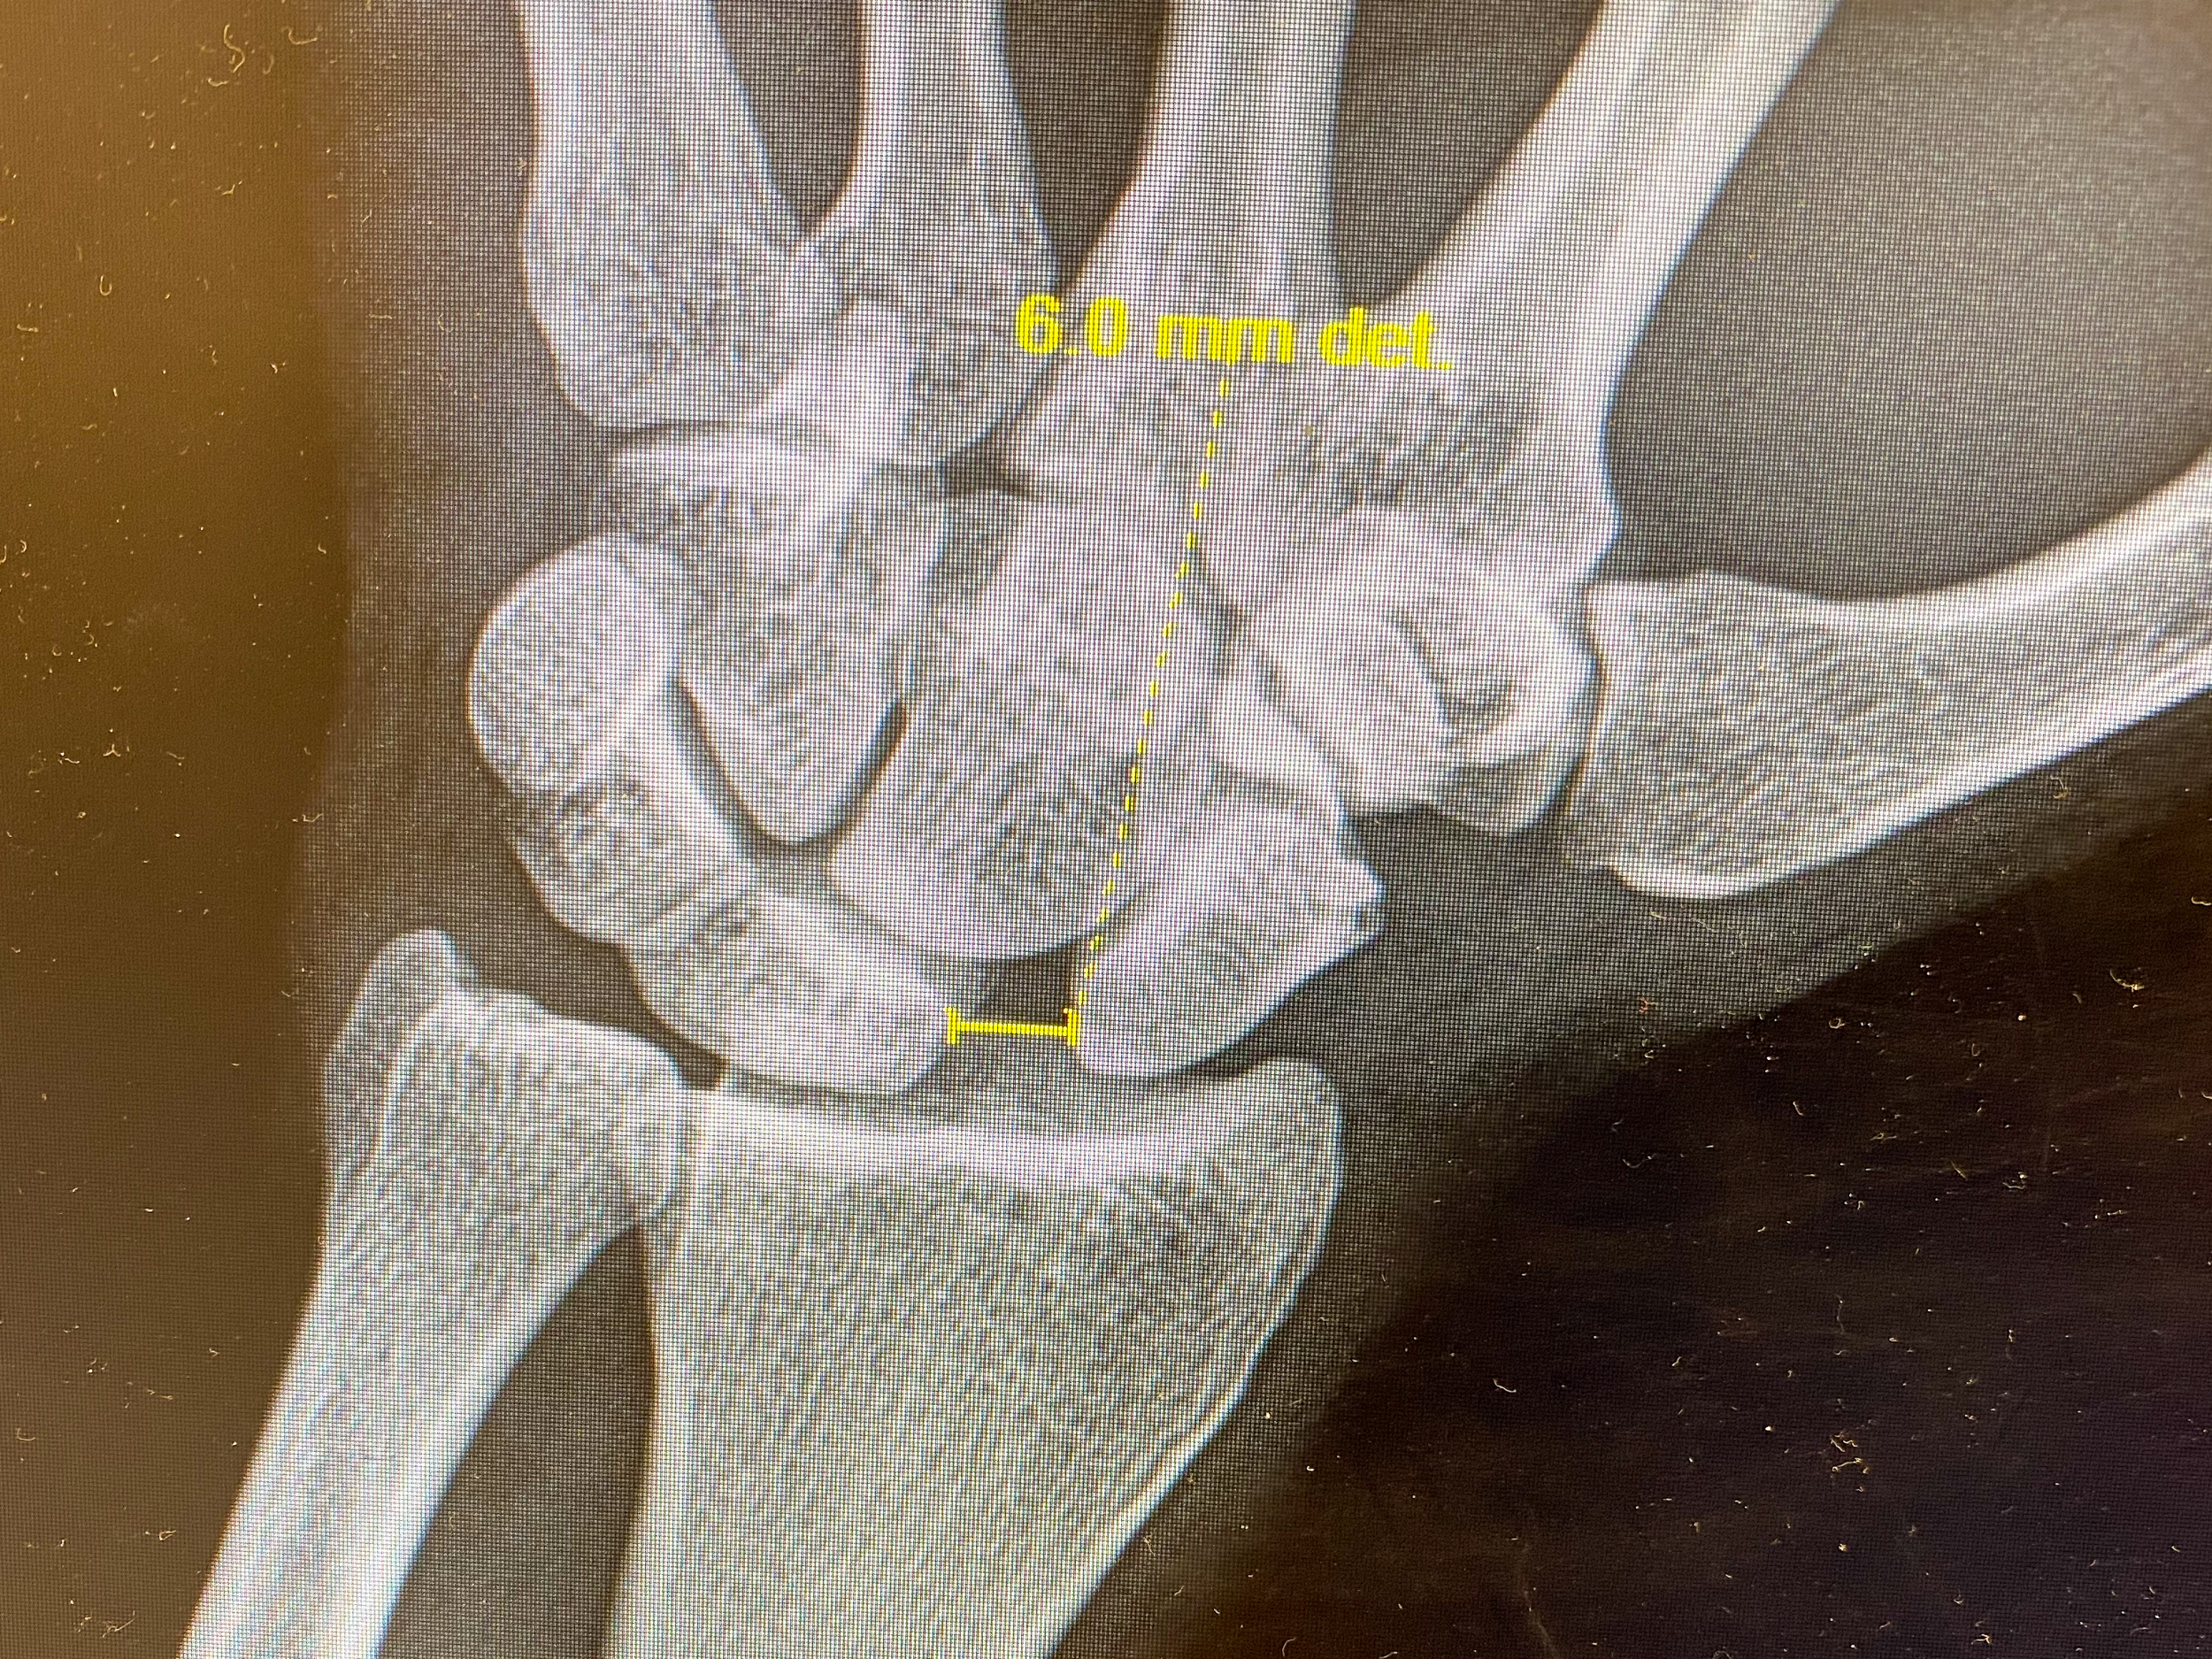

A few months later, I crashed while dirt biking, resulting in 11 knee procedures plus two staph infections and a wrist reconstruction. I was put on suicide watch during one of the hospital stays, being the statistically significant “hospital suicide risk.”